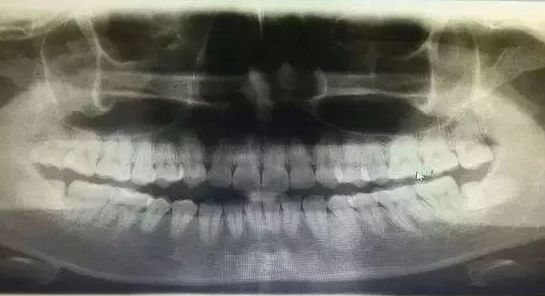

Step2 拍牙片

一般拔牙前,醫生會俾你拍個牙片。

拍牙片的目的是爲了看清楚牙根的生長情況。例如:智齒,佢哋身型萬千。瞭解清楚智齒的生長的情況,先會喺拔牙嘅時候適度用力,避免損傷鄰牙。